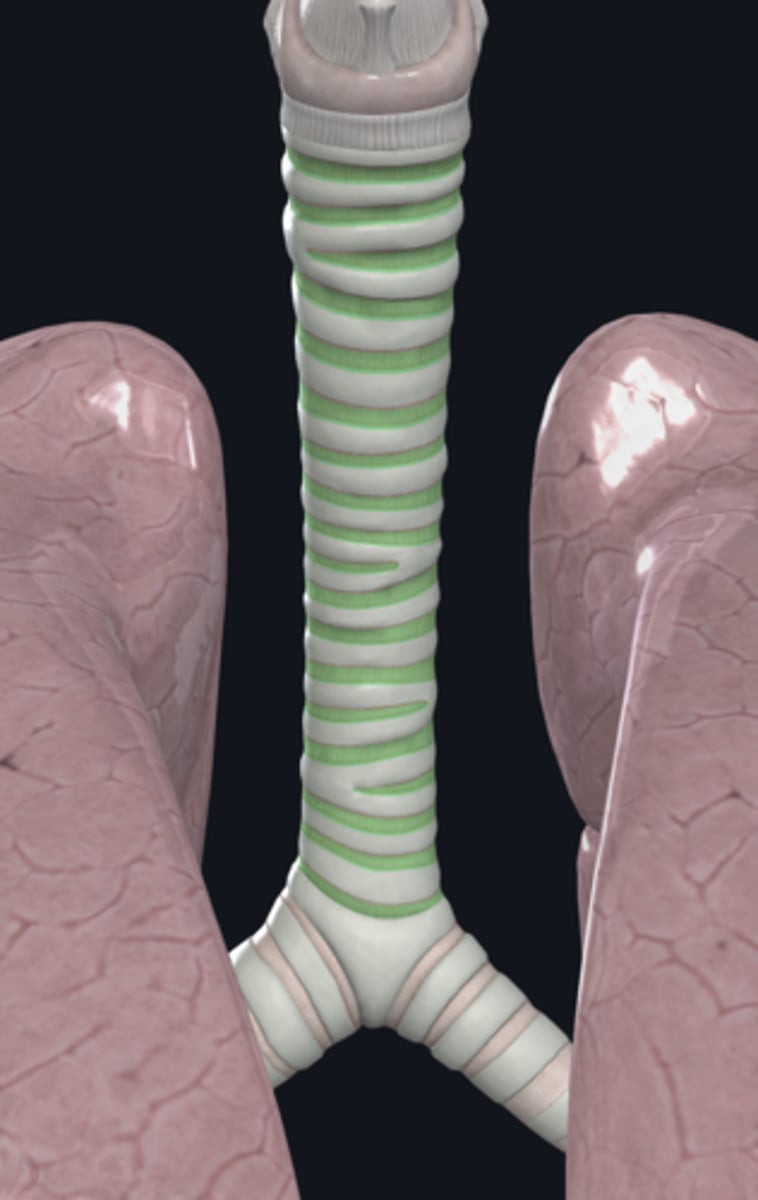

trachea

tracheal cartilage

trachea

tracheal cartilages

annular ligament

right main bronchus

left main bronchus

lobar bronchi

terminal bronchi